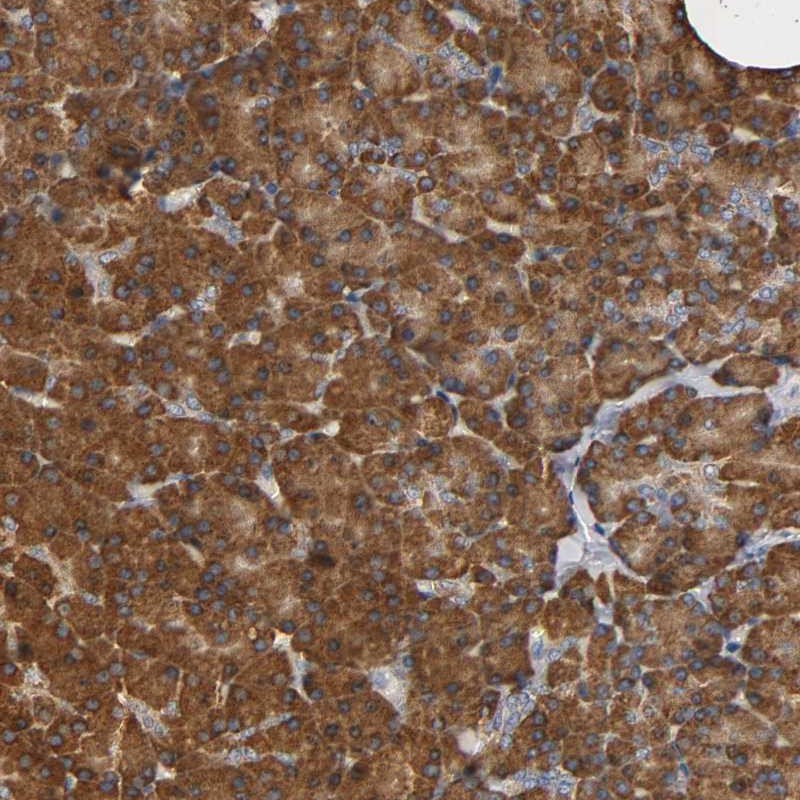

NDUFS3